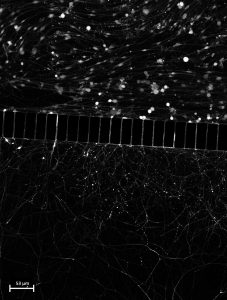

TÍTULO DE LA IMAGEN (traducido por la organización): Laberintos microcósmicos: neuronas y axones en armonía fluídica

AUTORA: Angela Lamberti

TEXTO ARTÍSTICO-DIVULGATIVO

(traducido por la organización) Mapeo de redes neuronales: neuronas sensoriales del ganglio de la raíz dorsal (DRG) cultivadas en cámaras de microfluidos. En su interior, los microcanales sirven como arterias para la navegación axonal. Abajo, la congestión axonal crea una semejanza con el paisaje urbano, reflejando las complejidades del tráfico neuronal: un vívido microcosmos de vida pintado en un lienzo en miniatura.

TÍTULO DE LA IMAGEN (traducido por la organización): Una sinfonía silenciosa de dolor neuropático

(traducido por la organización) En este lienzo en miniatura, las neuronas sembradas en la cámara de microfluidos superior extienden sus axones, solo para retraerse bajo la influencia de la quimioterapia. Esta delicada danza refleja la experiencia humana, capturando la conmovedora lucha y resiliencia dentro de nuestros propios cuerpos.